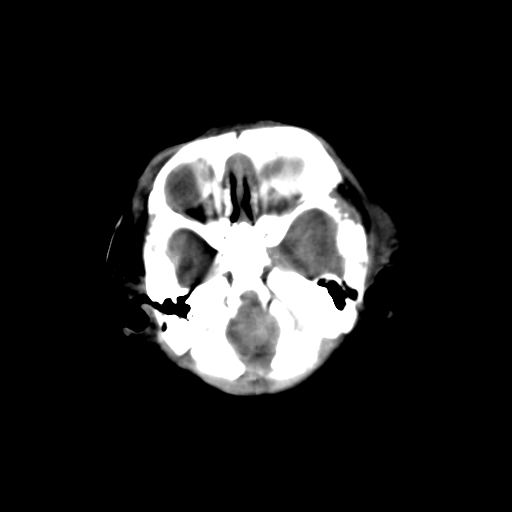

男,3天,患儿为剖腹产,生后嗜睡、拒乳。

1)考虑hie。2)sah?。3)右侧颞顶枕部及左侧颞顶部头皮血肿。

1、右侧颞顶枕部及左侧颞顶部头皮血肿。2、第五第六脑室。3、新生儿,脑白质密度还算可以,也无蛛血,不考虑hie。

脑室系统及脑沟裂闭塞,弥漫性脑密度减低,支持考虑hie,建议复查。右侧颞顶枕部及左侧颞顶部头皮血肿,另不除外胼胝体发育不良,复查